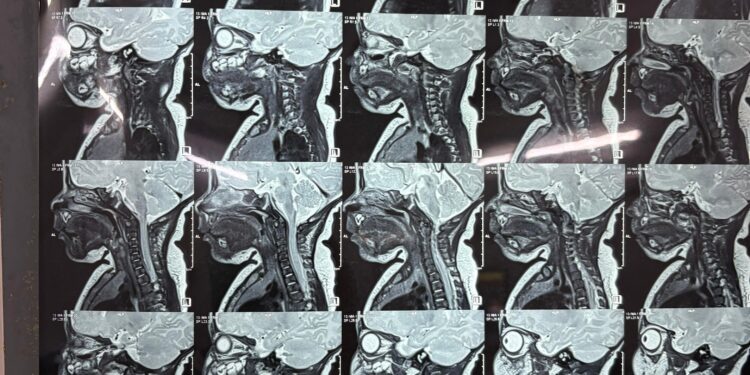

Following the delivery, doctors at the hospital referred the newborn to renowned paediatric surgeon Dr. Aniruddha Basak for specialised evaluation. When the baby was just 17 days old, Dr. Basak recommended a series of diagnostic tests to determine the severity of the condition. During this period, the cyst began to enlarge at an unusual and alarming rate, leaving the parents deeply worried and prompting an urgent return to the specialist with the test results.

The infant was admitted on November 21, and after thorough assessment, stabilisation, and preparation, the surgical team scheduled the operation for November 25. The delicate procedure lasted two hours and was carried out with precision, resulting in a successful outcome without any complications—an extraordinary feat considering the age of the patient and the technical challenges involved.